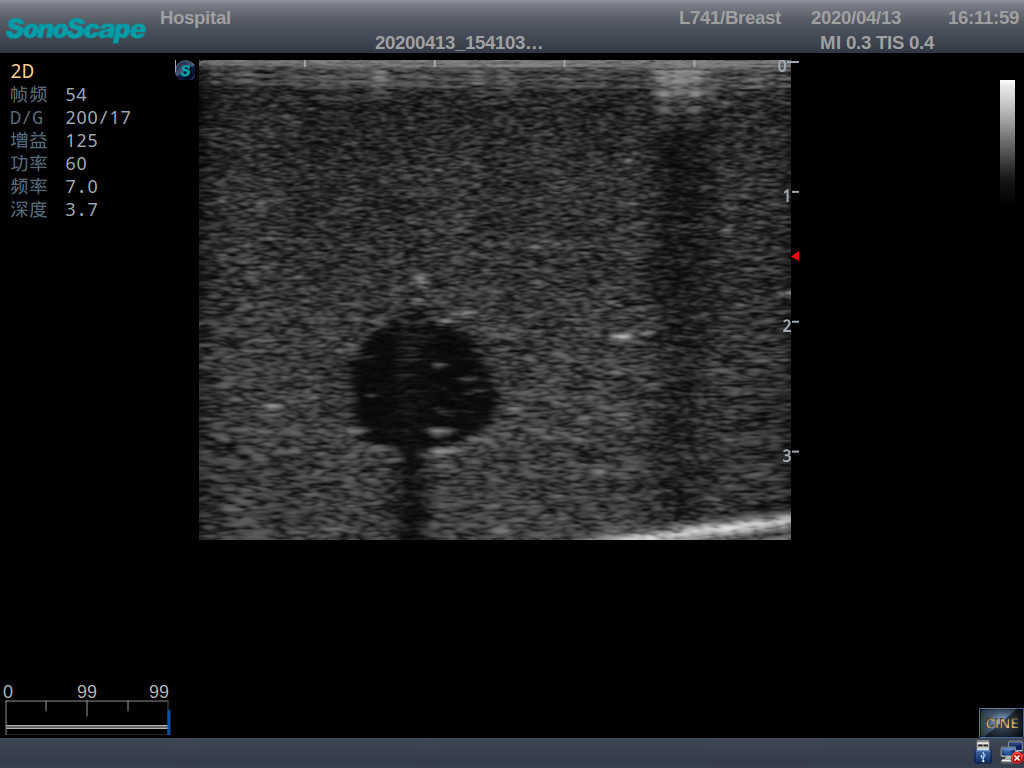

4) Biomimetic material allowing users to see clear and real normal tissues and space-occupying lesions that are hyperechoic, hypoechoic and isoechoic as they would see in the clinical environment